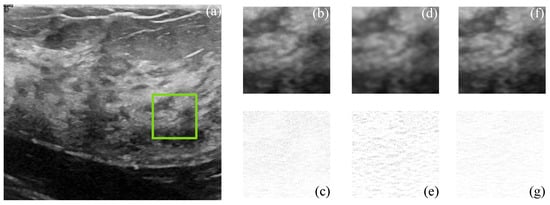

Figure 9 and Figure 10 show the actual filtered ultrasound images, named US-07 and US-20, respectively, with the subjective visual comparison of the proposed CMI-3DSVD against the BM3D and DLRA methods.

Figure 9 and Figure 10 show that the proposed approach provides high-quality despeckled images compared to the BM3D and DLRA methods. Moreover, as noticed in the error images, the DLRA filter causes blurring in detailed areas. This drawback resides in the lack of consideration of statistical properties for 3D group creation and the use of the Euclidean distance to measure the similarity between patches, which may cause alteration of the edges’ properties of the processed 3D block. In opposition, the CMI-3DSVD filter achieves better performance since it preserves edge quality and does not deform homogeneous regions in the processed images.

Figure 10. Subjective visual results of the despeckled real US image US-20. (a) Input image. Details are taken from the region marked in green: BM3D: (b) despeckled image, PSNR = 25.48 dB, EPI = 0.6872; (c) error image. SD-BM3D: (d) despeckled image, PSNR = 26.01 dB, EPI = 0.7158; (e) error image. CMI-3DSVD: (f) despeckled image, PSNR = 26.33 dB, EPI = 0.7396; (g) error image.